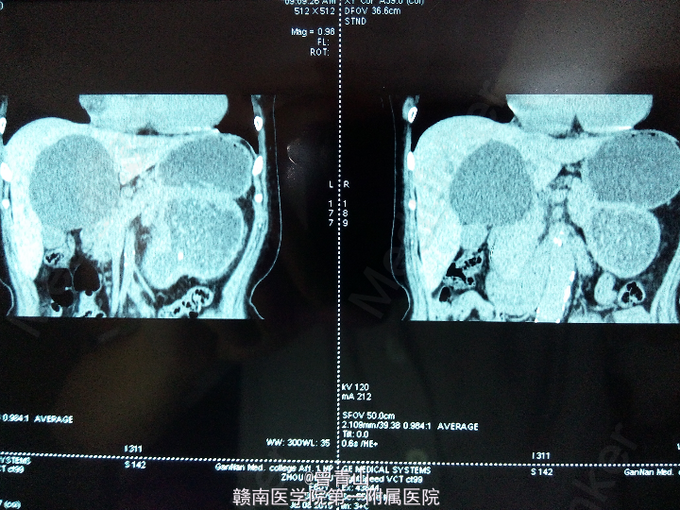

查体无异常。腹部彩超示:肝囊肿87×66mm。腹部增强CT提示肝囊肿。

诊断为肝囊肿。在全麻下行腹腔镜下囊肿开窗术。

术后病理证实为孤立性肝囊肿。单纯性肝囊肿为先天性、非遗传性肝内囊性病变。囊腔通常不与肝内胆管系交通,囊肿是由上皮细胞排列组成的闭合腔隙,内含液体,可为单发性或多发性。